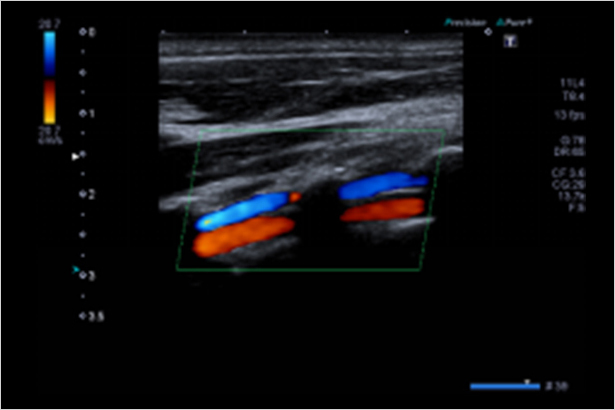

ADF运用宽频带窄脉冲技术让多普勒成像模式具有敏感度和空间分辨率